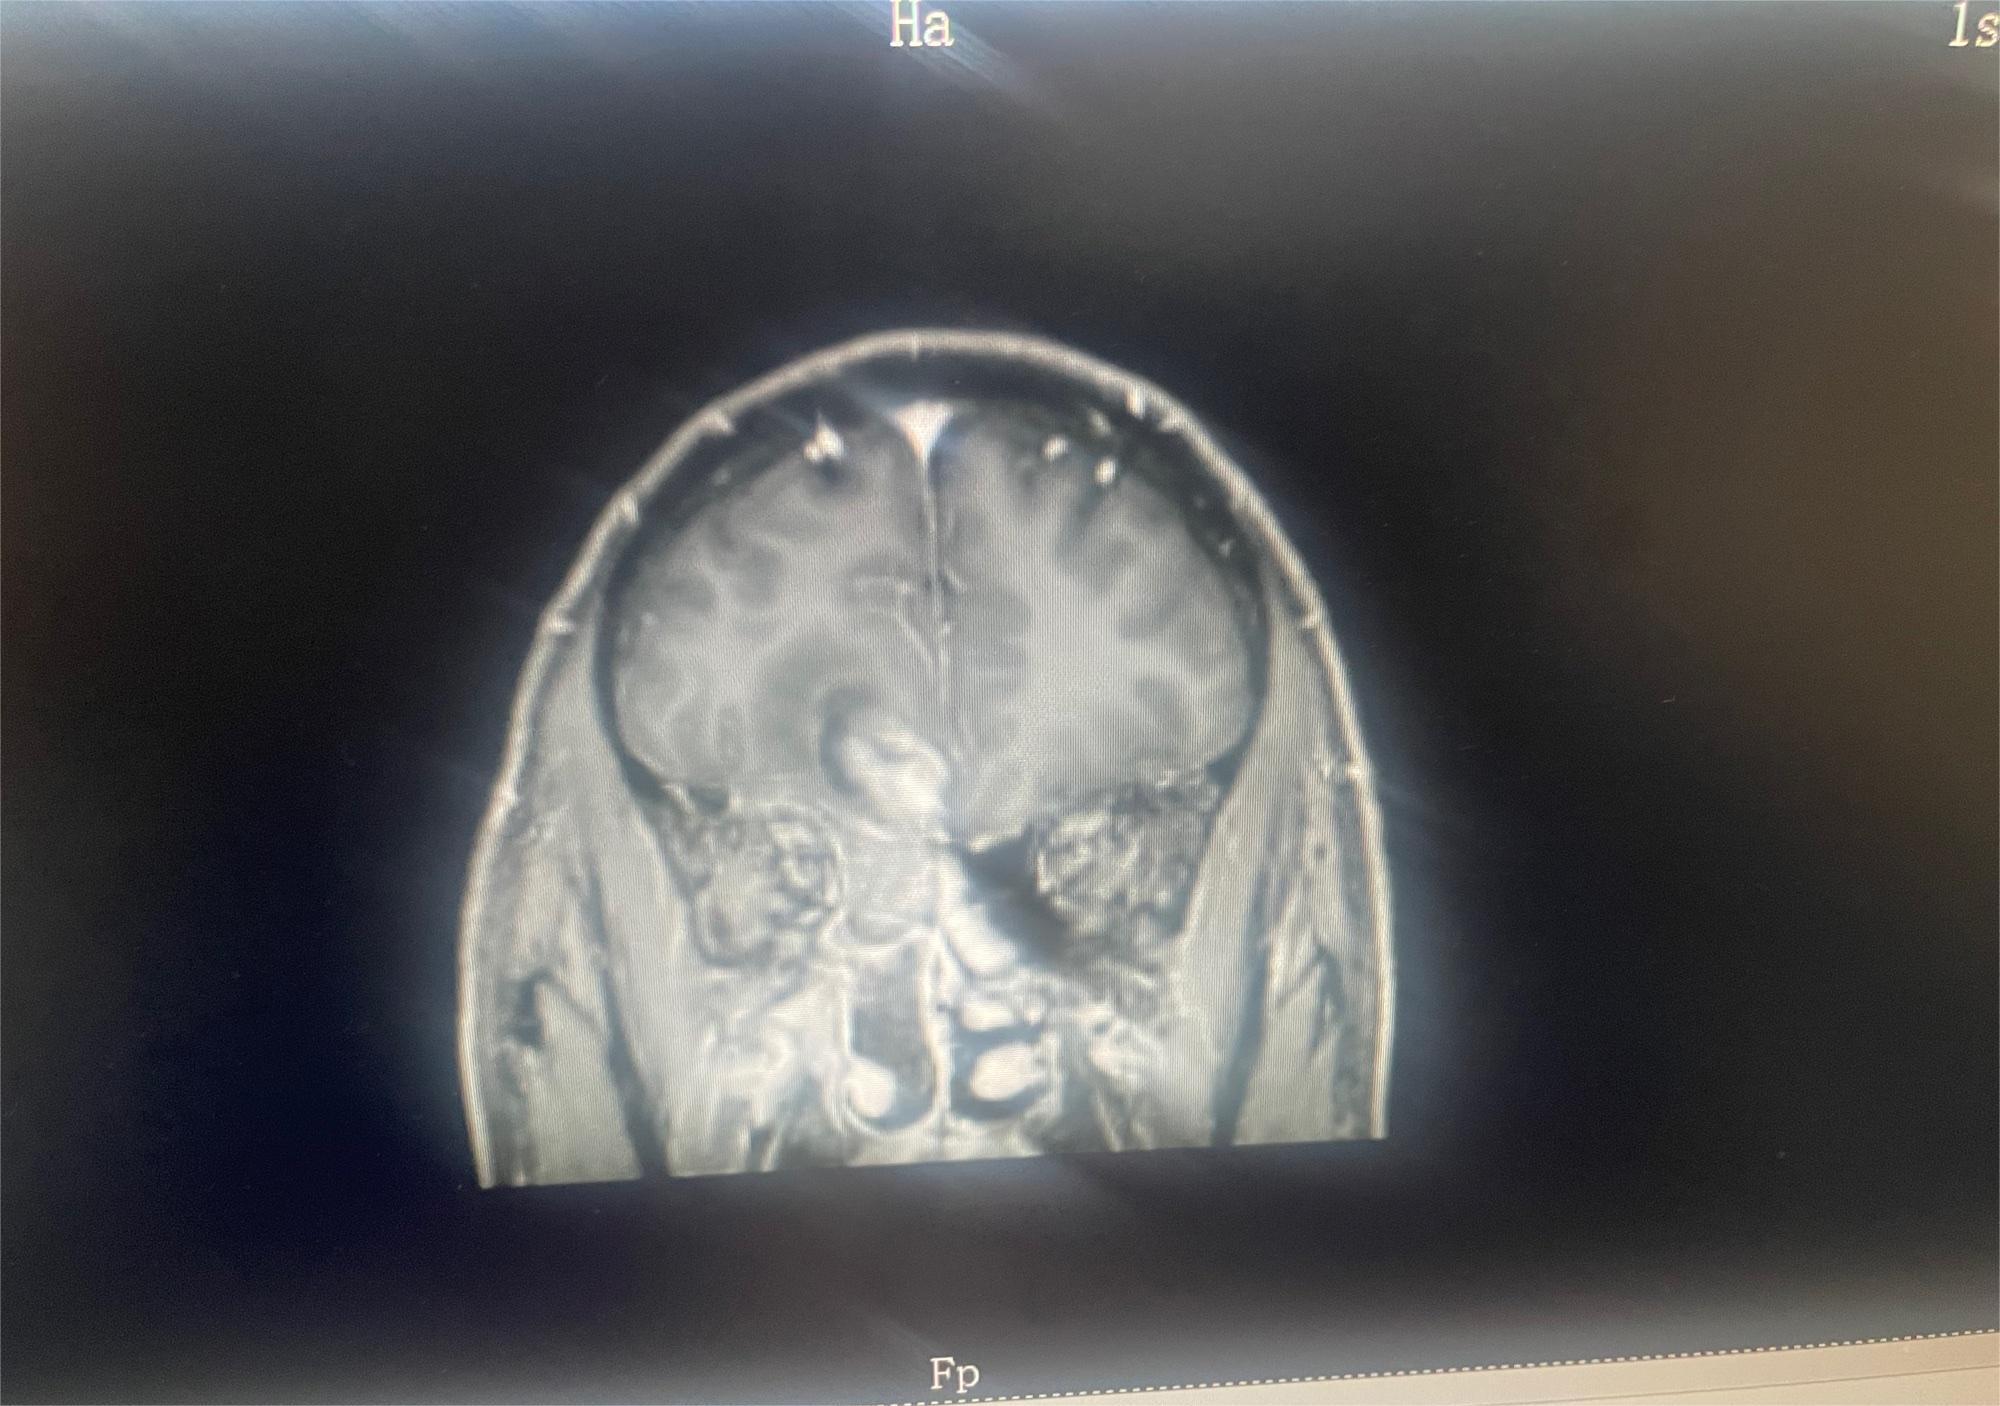

Kawahi 02025-01-07 患者家属肿瘤主要位于脑干,医生都说做不了切除手术,现在做了活检,准备去做放疗,但也几乎无济于事,不知道还会不会有可能有其他治疗方...

幻灭人海 02024-11-19 患者家属我妈妈确诊脑胶质瘤,现在在沧州中心医院脑科,医生说恶性程度很高,手术肯定瘫痪,建议保守治疗,我弟去了天津肿瘤医院,让做M...